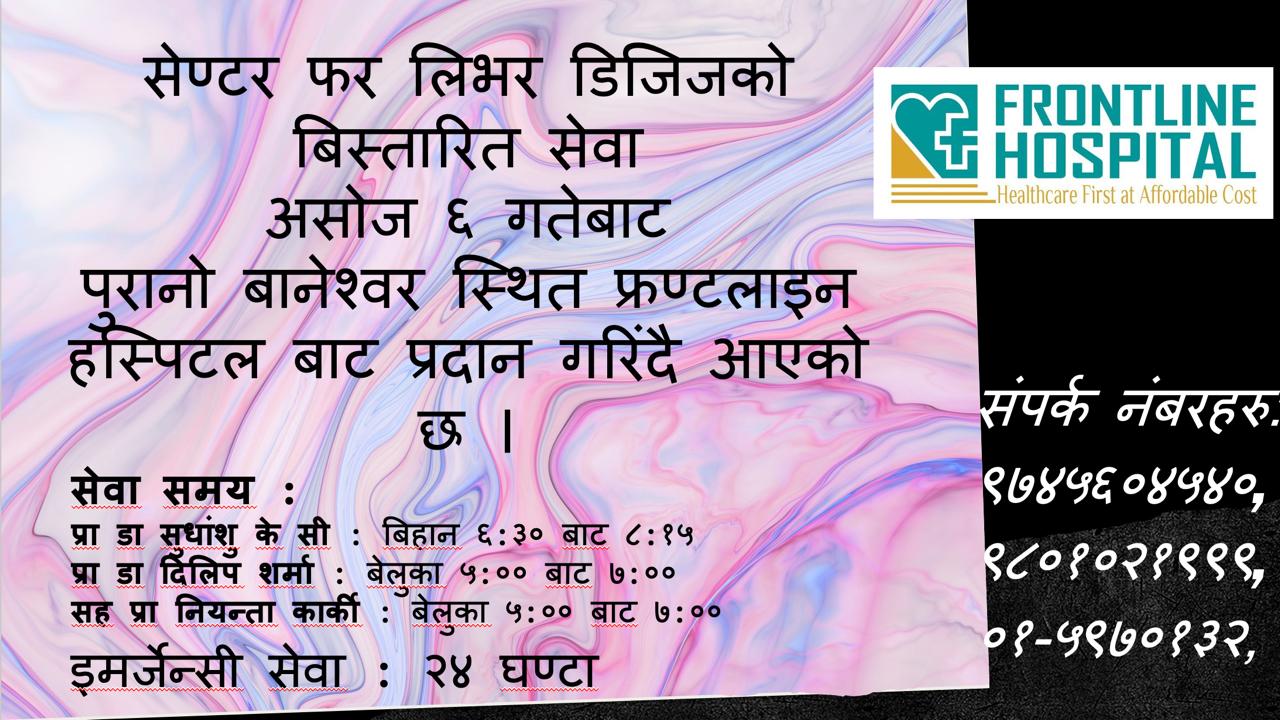

- Liver clinic

- Surgical consultations for surgical hepatobiliary diseases

- Hepatitis clinic

- Vaccination services

- Fibroscan

- Liver biopsy

- Diagnostic and therapeutic hepatobiliary ultrasound

- Doppler study of portal system and hepatic veins

- Diagnostic and therapeutic upper GI endoscopy

- All types of laboratory test for liver diseases

- Pre liver transplantation work up and post transplantation follow up

- New tests Available

- HBV DNA quantitative

- HCV RNA quantitative and genotyping

- HFE gene mutation test